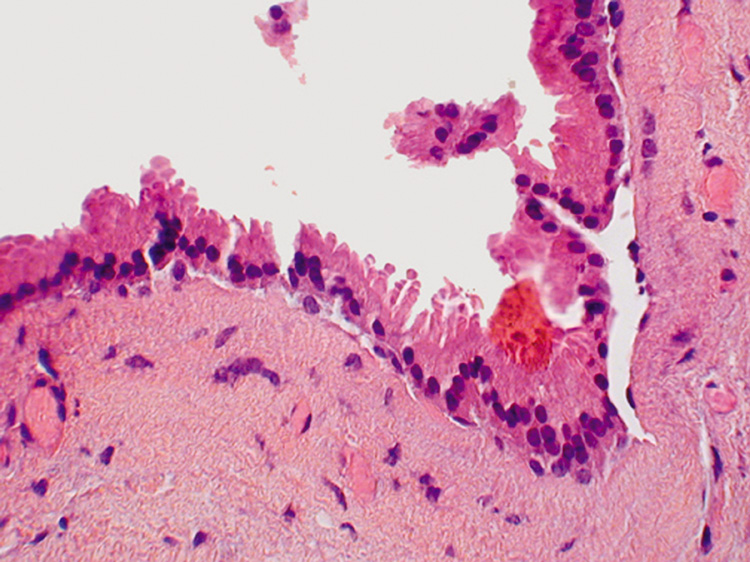

Umbilicated vesicles on an erythematous base progressing to pustules and crusted papules are characteristic of generalized vaccinia (small pox), with new cases recently reported secondary to the small pox vaccine. These vesicles are also characteristic of varicella (chickenpox), herpes zoster (shingles), and primary and recurrent herpes simplex infections (Fig. 6A). Herpesviruses are DNA-containing viruses that infect host cell nuclei resulting in similar, characteristic histologic changes. There is marked intraepidermal vesiculation and necrosis with massive ballooning and rupture of keratinocytes, spongiosis, acantholysis, and a dense superficial dermal perivascular lymphohistiocytic infiltrate with neutrophils, which also are seen commonly infiltrating the epidermis. Multinucleated epithelial giant cells with nuclei, which are steel gray and demonstrate peripheral margination of clumped chromatin material, are characteristic of early and well-developed vesicles (see Fig. 6B). Progression to near total epidermal necrosis makes these characteristic cells more difficult to identify. Occasionally, eosinophilic staining and small intranuclear inclusions may be visible. A Tzanck smear may be obtained by unroofing a vesicle, scraping the base, and staining the base with Giemsa stain. This rapid diagnostic method enables identification of multinucleated epithelial giant cells and single keratinocytes with characteristic nuclear changes.

Fig. 6. A. Recurrent herpes simplex infection with umbilicated pustulovesicles on an erythematous base. B. Herpes simplex infection with intraepidermal vesicle containing characteristic multinucleated epithelial giant cells.